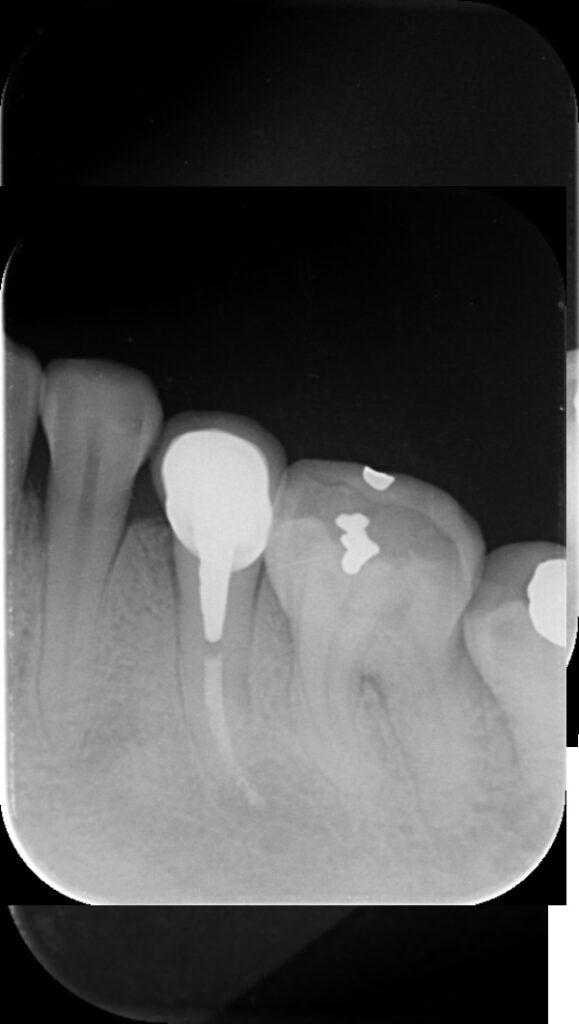

Cas très spécial = 2 lésions osseuses (rond noir)

Traitement en cours = Longueur OK

Final J0

Radio à 1 an = C’est gagné ! ( pour l’instant! )